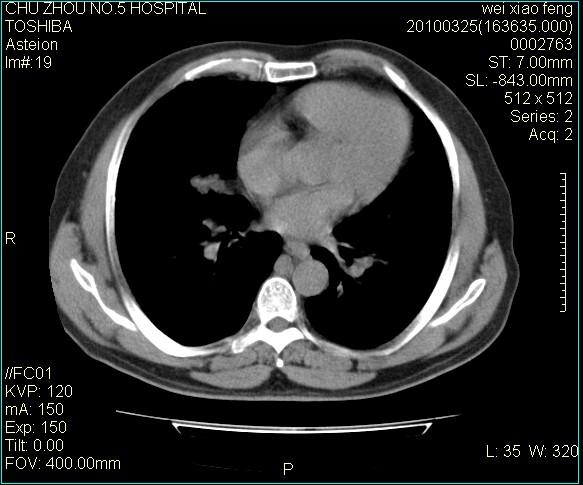

男,60岁,反复咳、痰、喘3月,加重3天。

双肺间质性改变。

考虑双肺血型潘散肺结核/

间质性肺炎伴间质纤维化!不排除伴有职业病!

急性血型潘散肺结核。

双肺间质纤维化,双肺血型潘散肺结核。

心功能怎么样?感觉象肺淤血。

考虑间质性肺炎伴间质纤维化。

肺泡癌不除外

右肺中叶结节影为原发灶,考虑右肺中叶周围型肺癌并淋巴道转移